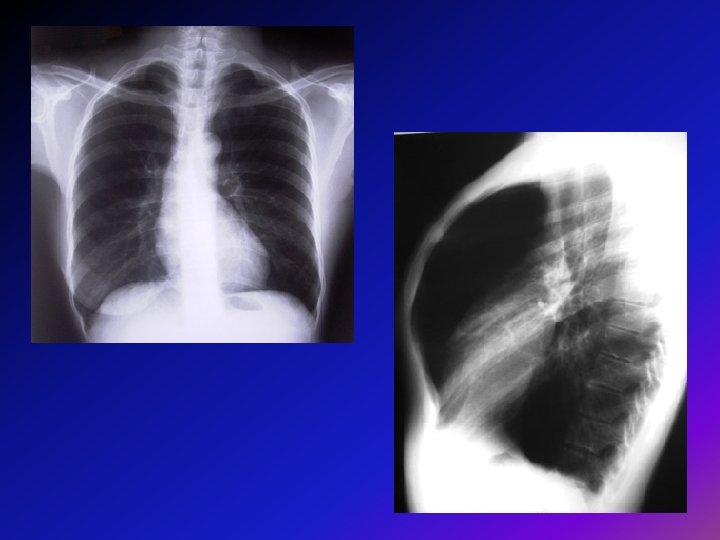

• Radiografía de Tórax: es de ayuda para descartar otros diagnósticos como ICC o para identificar lesiones bullosas y también para el diagnóstico de EPOC. • Hallazgos en EPOC: -Diafragma bajo y aplanado. -Aumento del espacio retroesternal. -Corazón en forma de lágrima.